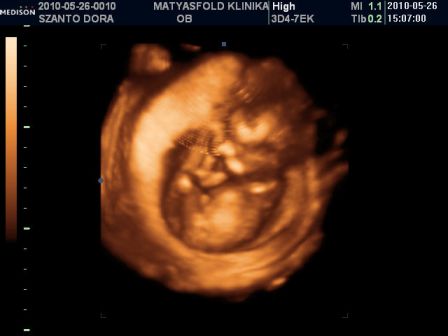

És, holnap délután 4-re megyek anyuval 4D-s uh-ra! Uram Pakson lesz, nem biztos, h addigra hazaér... :( De kiírják DVD-re, meg lesznek képek is! :D Most még mindig a genetika a fő lényege a dolognak, meg állítják, h a 13. hét után megmondják a bébi nemét. :D Hát, kíváncsi leszek... :twisted: Csütörtökön lépek a 15. hétbe, szóval az esély megvan! :D

Mi megjöttünk az uh-ról! :D Uram sajna nem ért oda :(, de mi mamával áhitattal néztük Manó Gyereket fél órán keresztül! :D

Hála az égnek, minden rendben van, mindene megvan és működik is, minden tökéletes méretű rajta! Kóros elváltozás sehol nem látható! (A dvd-t most fogjuk megnézni büszke apájával... :wink: )

Kép

...Uram gazdagabb lett 10 Ft-tal... :oops: :cry: :twisted: :P

KISFIÚ!!! Ennyit a megérzésemről... :? :cry: :wink: :lol: Üdv a pocakomban Dániel Áron! :D